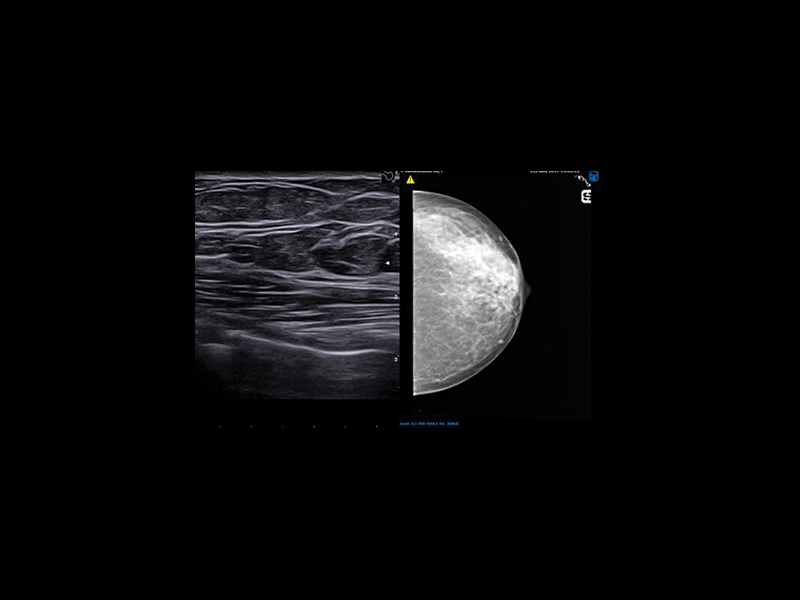

Second-look & Follow up

BreastNav™ & BreastNav™ MRI offer the full breast package for a multimodality approach in one of the most mobile and variable organs in the human body, giving real-time feedback on the scanned area for easy follow-up on a specific target.

BreastNav™ is an advanced technology based on adaptive 3D modeling, which enables quick, easy and effective follow-up of breast lesions, clip insertion, injury, or to provide an indication to the surgeon with regard to location.

BreastNav™ MRI is a unique feature in the market, which can perform real-time fusion imaging on the breast between the prone MRI and supine US datasets, based on 3D-model adaptive A.I. technology, aimed at supporting second-look examinations.

BreastNav™ & BreastNav™ MRI, Second-look & Follow up